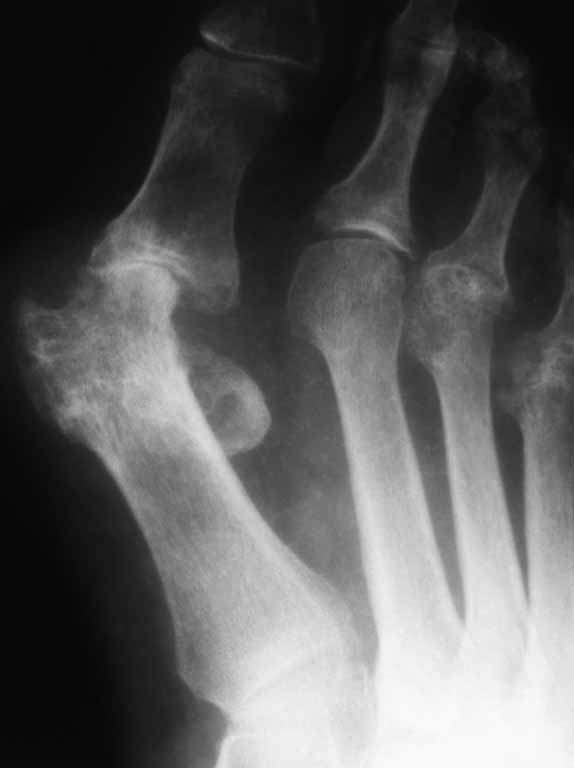

Дефартроз первого плюснефалангового сочленения.

55 лет. Ревматоидный полиартрит.

Артродез или протез ПФС?

А если посоветуют протез? Уверены, что сумеете добиться стабильного протезирования при таком дисконгруэнтном суставе? Артродез кажется более очевидным решением. Но и здесь могут быть сложности. Хоть стопа и не вся на рентгенограмме, видно, что имеется нестабильность 3 и 4 плюснефаланговых суставов. Артродез 1-го плюснефалангового без коррекции 1-го межплюсневого угла приведет к еще большему относительному укорочению 1 плюсневой. А это ускорит дестабилизацию латеральных лучей и спровоцирует развитие переходной центральной метатарсалгии. Мне кажется, что в подобной ситуации можно было бы обдумать вариант артродеза медиального плюснеклиновидного сустава или какой-либо из коррегирующих остеотомий 1 плюсневой (на Ваш вкус). Либо нужно совмещать артродез 1 плюснефалангового с вмешательством на латеральных лучах. Хотя, без полноценных рентгенограмм и фотографий стопы, не зная, что беспокоит пациента, с какой скоростью развивалась данная деформация, есть ли нестабильность медиального плюснеклиновидного сустава и т.д., советовать сложно.

Это скорее не стеоартроз, а проявление основного заболевания - ревматоидный артрит характеризуется эрозированием суставных повернхностей, что видно на рентгенограмме.

Протезирование 1 пф сустава выполнять не следует хотя бы потому, что больные РА постоянно получают гормонотерапию, что вызывает выраженный остеопороз. "Золотой" стандарт в таких случаях артродез 1 пф сустава+резекция головок 2-5 плюсневых костей